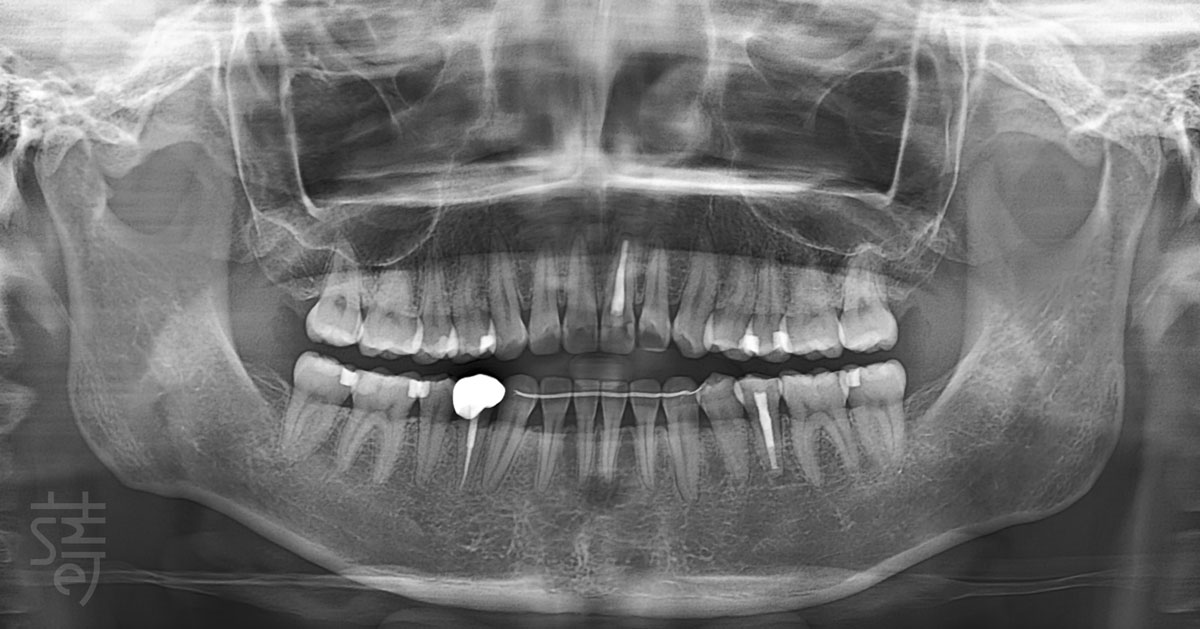

在進入貼片設計之前,林醫師先為張小姐進行一次完整而細緻的檢查。

一個真正成熟的瓷牙貼片美學設計,必須同時兼顧多個層面,而非單點修飾。

林醫師評估的重點,至少包含以下六個關鍵維度:

① 牙齒牙齦的健康狀態

② 齒色的層次與透亮度

③ 牙齒牙齦型態及比例

④ 整體排列與微笑曲線

⑤ 動態笑容的肌肉運作

⑥ 最終形塑的風格感受

這些元素彼此牽動,缺一不可。

也因此,蒔美團隊透過一系列數位化檢測,從口內結構、臉部比例到肌肉運作層面,全面檢視張小姐的口內外條件。當所有基礎被妥善整理後,瓷牙貼片的設計與療程,才正式展開。

Before any veneer design began, the Smile Dental team conducted a thorough evaluation. A truly considered veneer plan looks beyond surface fixes—assessing dental and gum health, shade and translucency, proportions, smile line, muscle movement, and overall style.

Health always comes first. Only after confirming the mouth can support veneers long term did the Smile Dental team move forward, using digital tools to assess everything from oral structure to facial balance. With the foundation in place, the aesthetic work could begin.

過去左上門牙曾因童年蛀牙接受根管治療與假牙修復,加上長期飲用咖啡,原生牙齒隨著時間逐漸染色,使整體齒色偏暗,並與假牙之間拉開色差。在不同光線下,笑容呈現出不均勻的層次感,成了她心中始終放不下的小細節。

蒔美團隊進一步透過臉部掃描與專業數位攝影,從多角度檢視她的臉型比例,以及動態與靜態下的微笑表現,並運用高階 DSD 微笑設計系統,將抽象的想像轉化為可視化,可具體討論的模擬畫面。

在瓷牙貼片設計中,牙齦比例往往是影響成敗的另一關鍵。為了讓整體效果更為自然,林醫師建議搭配牙齦微整形,重新調整牙齒與牙齦的視覺關係。

透過細緻的修整與貼片形態調整,原本略顯扁短的牙齒輪廓,得以重新取得視覺空間,讓長寬比例從接近一比一的方形,過渡至更接近五比四的和諧比例。